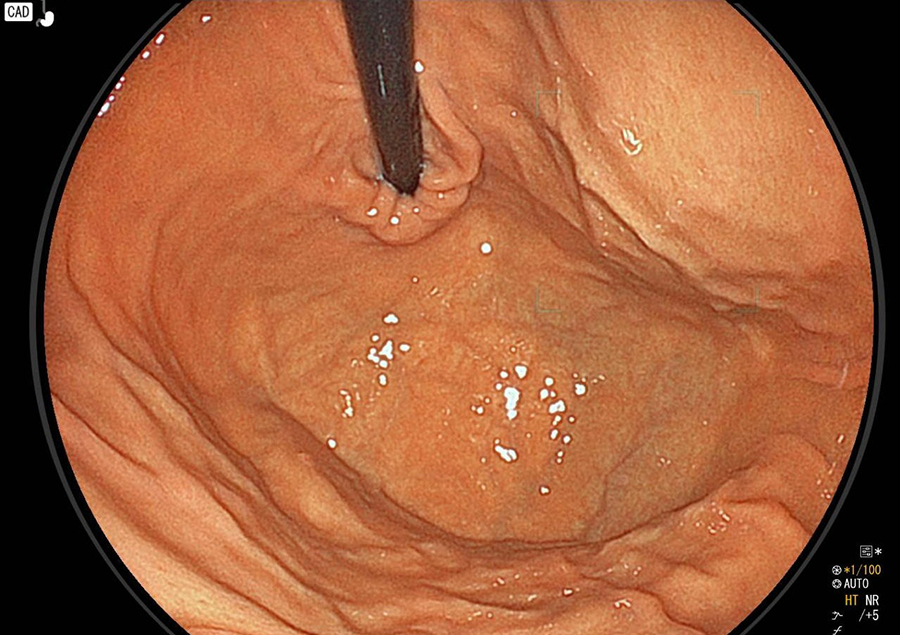

白色粘液付着

炎症によって白い粘液が付着し、胃のひだがむくんで腫れています。